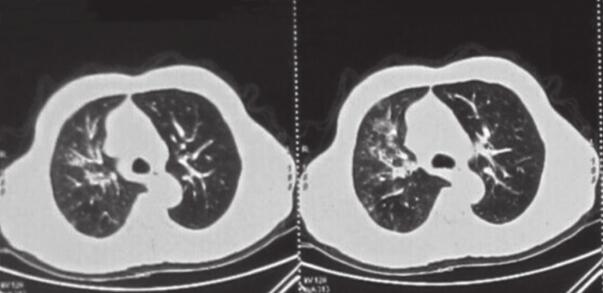

患者,刘某,男,66岁。因“反复咳嗽、咳痰2年余,再发加重3天”于2014年3月7日入院。自2012年以来,患者无明显诱因出现反复咳嗽、咳痰,多为白色泡沫痰,咳嗽剧烈时伴胸闷、气喘不适,间断高热,多次在外院住院治疗,每经抗感染及止咳祛痰等对症治疗后病情可缓解,出院后患者咳嗽、咳痰症状仍反复。自2012年起病以来,患者多次行肺部CT(图1~图4)检查提示“左下肺大片状及右上叶片状阴影”,行抗感染治疗后右肺上叶稍吸收,左下肺片状影吸收欠佳。2013年8月考虑患者“肺结核”不能排除,在本市结核病医院,查T-spot(+),后给予三联抗结核(异烟肼+利福平+乙胺丁醇)治疗2个月,咳嗽、咳痰未见明显好转。2013年11月曾因咳嗽、咳痰加重入我科,给予抗感染(左氧氟沙星)及继续抗结核(异烟肼+利福平+乙胺丁醇)治疗,期间患者因大便潜血(+)行肠镜检查,提示“乙状结肠直肠新生物”,病理检查示“乙状结肠腺癌”,于2013年12月8日转普外科行“乙状结肠癌根治术”。此次入院前3天,患者受凉后再发咳嗽,咳白色泡沫痰,量较多,偶为粉红色泡沫痰,咳嗽剧烈时感憋气、胸痛,无畏寒、发热,无恶心、呕吐,无双下肢水肿等不适。

图1 2013年1月7日右上肺(A)及左下肺(B)